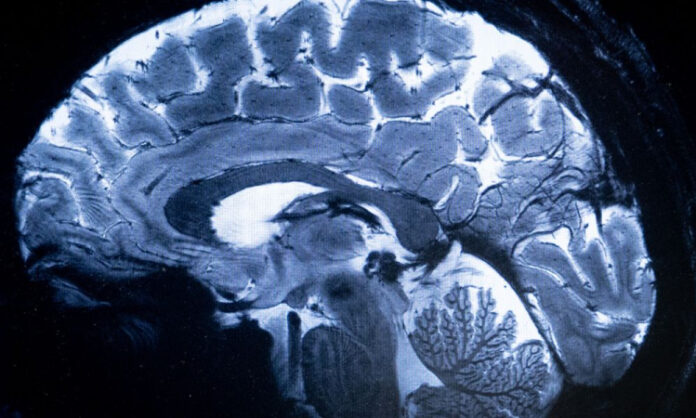

Pesquisadores esperam que o poder do scanner também lance luz sobre os mecanismos ocultos por trás de doenças neurodegenerativas

O scanner de ressonância magnética (IRM) mais potente do mundo conseguiu escanear o cérebro com um nível de precisão jamais visto, uma proeza que pode ser decisiva para detectar doenças. “Vimos um nível de precisão nunca antes alcançado no CEA”, disse Alexandre Vignaud, um físico que trabalha no projeto. Pesquisadores da Comissão de Energia Atômica (CEA) francesa utilizaram pela primeira vez a máquina para escanear uma abóbora em 2021. Recentemente, as autoridades sanitárias deram sinal verde para escanear humanos, e cerca de 20 voluntários saudáveis se ofereceram para que seus cérebros fossem escaneados em Saclay, subúrbio ao sul de Paris.

O campo magnético criado pelo scanner é de 11,7 teslas, uma unidade de medida nomeada em homenagem ao inventor Nikola Tesla. Essa potência permite que a máquina escaneie imagens 10 vezes mais precisas que os IRM normalmente utilizados em hospitais, cuja potência geralmente não supera os três teslas. “Com essa máquina podemos ver os pequenos vasos que alimentam o córtex cerebral, ou detalhes do cérebro que eram quase invisíveis até agora”, disse.

O produto é o resultado de duas décadas de pesquisa de uma parceria entre engenheiros franceses e alemães. Os Estados Unidos e a Coreia do Sul estão trabalhando em máquinas IRM igualmente potentes, mas ainda não começaram a escanear imagens de humanos. Um dos principais objetivos é multiplicar nossa compreensão da anatomia do cérebro e quais áreas são ativadas quando se realiza tarefas particulares.

Os pesquisadores esperam que o poder do scanner também lance luz sobre os mecanismos ocultos por trás de doenças neurodegenerativas, como Parkinson ou Alzheimer, ou problemas psicológicos, como depressão ou esquizofrenia. “Por exemplo, sabemos que uma área específica do cérebro, o hipocampo, está envolvida na doença de Alzheimer, por isso esperamos poder descobrir como as células dessa parte do córtex cerebral funcionam”, disse a pesquisadora do CEA Anne-Isabelle Etienvre. Os cientistas também esperam mapear como certos medicamentos usados para tratar o transtorno bipolar, como o lítio, são distribuídos pelo cérebro.